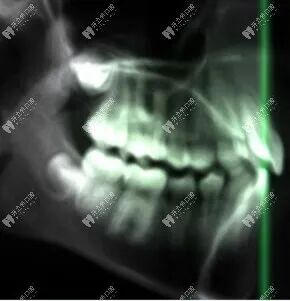

3、头颅侧位片

头颅侧位片主要展示颅骨和牙齿的侧方形态,通常拍摄全景片的机器也可以拍摄头颅侧位片。

这种牙片在正畸领域应用更为广泛,它为牙齿矫正提供重要的数据参考,可以帮助牙医清晰看到牙齿和骨头的相对关系,制定更加有效的矫正计划。